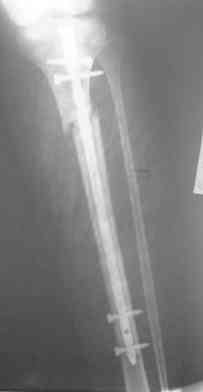

Re: Интрамедуллярный остеосинтез. Как избежать смещение?

конечно в данном случае все хорошо срастется.На будущее при таких высоких переломах,хорошо помогают направляющие винты.Они вводятся спереди назад(до введения стержня) для предотвращения бокового смещения или снуружи ввнутрь ,для предотвращения передне - заднего.Они не дают стержню сместить перелом.ЭОП не нужен,обычный рентген о опер.достаточен.

Удобнее для этих целей использовать спицы. Их и быстрее/легче ввести, и в случае слишком агрессивного введения они гнутся и удается провести гвоздь, в то время как с винтом он заклинится или расколется кость.